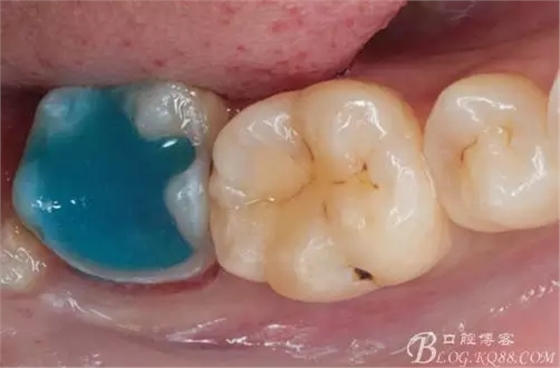

去除暫封物,拍照,比色。

流動樹脂充填窩洞,金霸王車針和鎢鋼車針常規(guī)備牙,配合硅膠尖拋光,頰側(cè)排00排齦線。硅橡膠二次法取模,記錄咬頜關(guān)系,臨時樹脂充填窩洞。